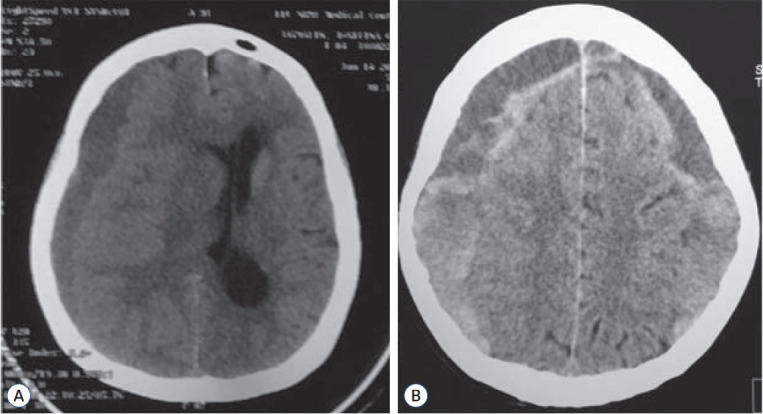

Results: In this study, a term 'mixed-type subdural hematoma' (MSDH) was proposed to encompass SDH that have mixed hypo-andhyperdensity on preoperative computed tomography scan and were subsequently found to have bright red liquefied hematoma instead of the classic engine machinery oil fluid found in a CSDH. Based on the observed cohort, nine out of 11 CSDH patients attained the Glasgow outcome scale extended (GOS-E) score of 8 while all the respondents in the MSDH group attained the same GOS-E score underscoring the need for early intervention in patients with non-acute SDH. Moreover, the outcomes of both MSDH and CSDH are comparable with low mortality rate (approximately 9.5%) and immediate postoperative improvement (approximately 90%).

Conclusion: MSDH and CSDH, although classified separately using clinical and/or radiologic means, can collectively be categorized as a non-acute SDH and can be managed safely and effectively with burr hole surgery.